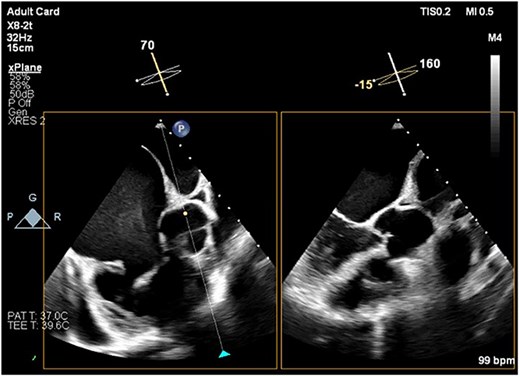

Preoperative transesophageal echocardiography (TEE) demonstrated marked RV and RA enlargement, severe RV systolic dysfunction, thickened RV walls, severe TR due to annular dilation, and severe PV stenosis. No ventricular septal defect was observed preoperatively (Figs 1–3). The left ventricle (LV) appeared small and D-shaped, consistent with elevated RV pressures (Table 1).

TEE image showing the short-axis view of the aortic valve and the corresponding long-axis view of the LV. There is no evidence of aortic overriding or septal defect. Note the spontaneous echo contrast smoke, representing slow blood flow, observed in the RA cavity.